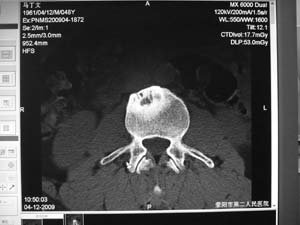

标题: MRI2131:男,腰痛三月向右下肢放射一月余 [打印本页]

标题: MRI2131:男,腰痛三月向右下肢放射一月余

骨质轻微破坏,硬化明显,椎管未见异常,考虑良性骨瘤的可能性大,

椎体增生 硬化 囊变。考虑:退变!

椎体前缘骨质增生硬化、囊变。椎旁软组织未见确切异常。考虑椎体前缘软骨结节。

1)l3椎体前上缘许莫氏结节形成。2)腰椎退行性改变。

l2大部分椎体信号增高-----脂肪变性,转移待排。l3 椎体t2 低信号考虑硬化增生。

腰3椎体骨样骨瘤.